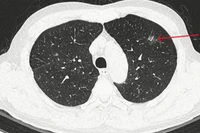

Những người thuộc nhóm nguy cơ cao cần khám lọc để phát hiện sớm, điều trị kịp thời và quản lý bệnh COPD hiệu quả. Ảnh: THẾ ANH